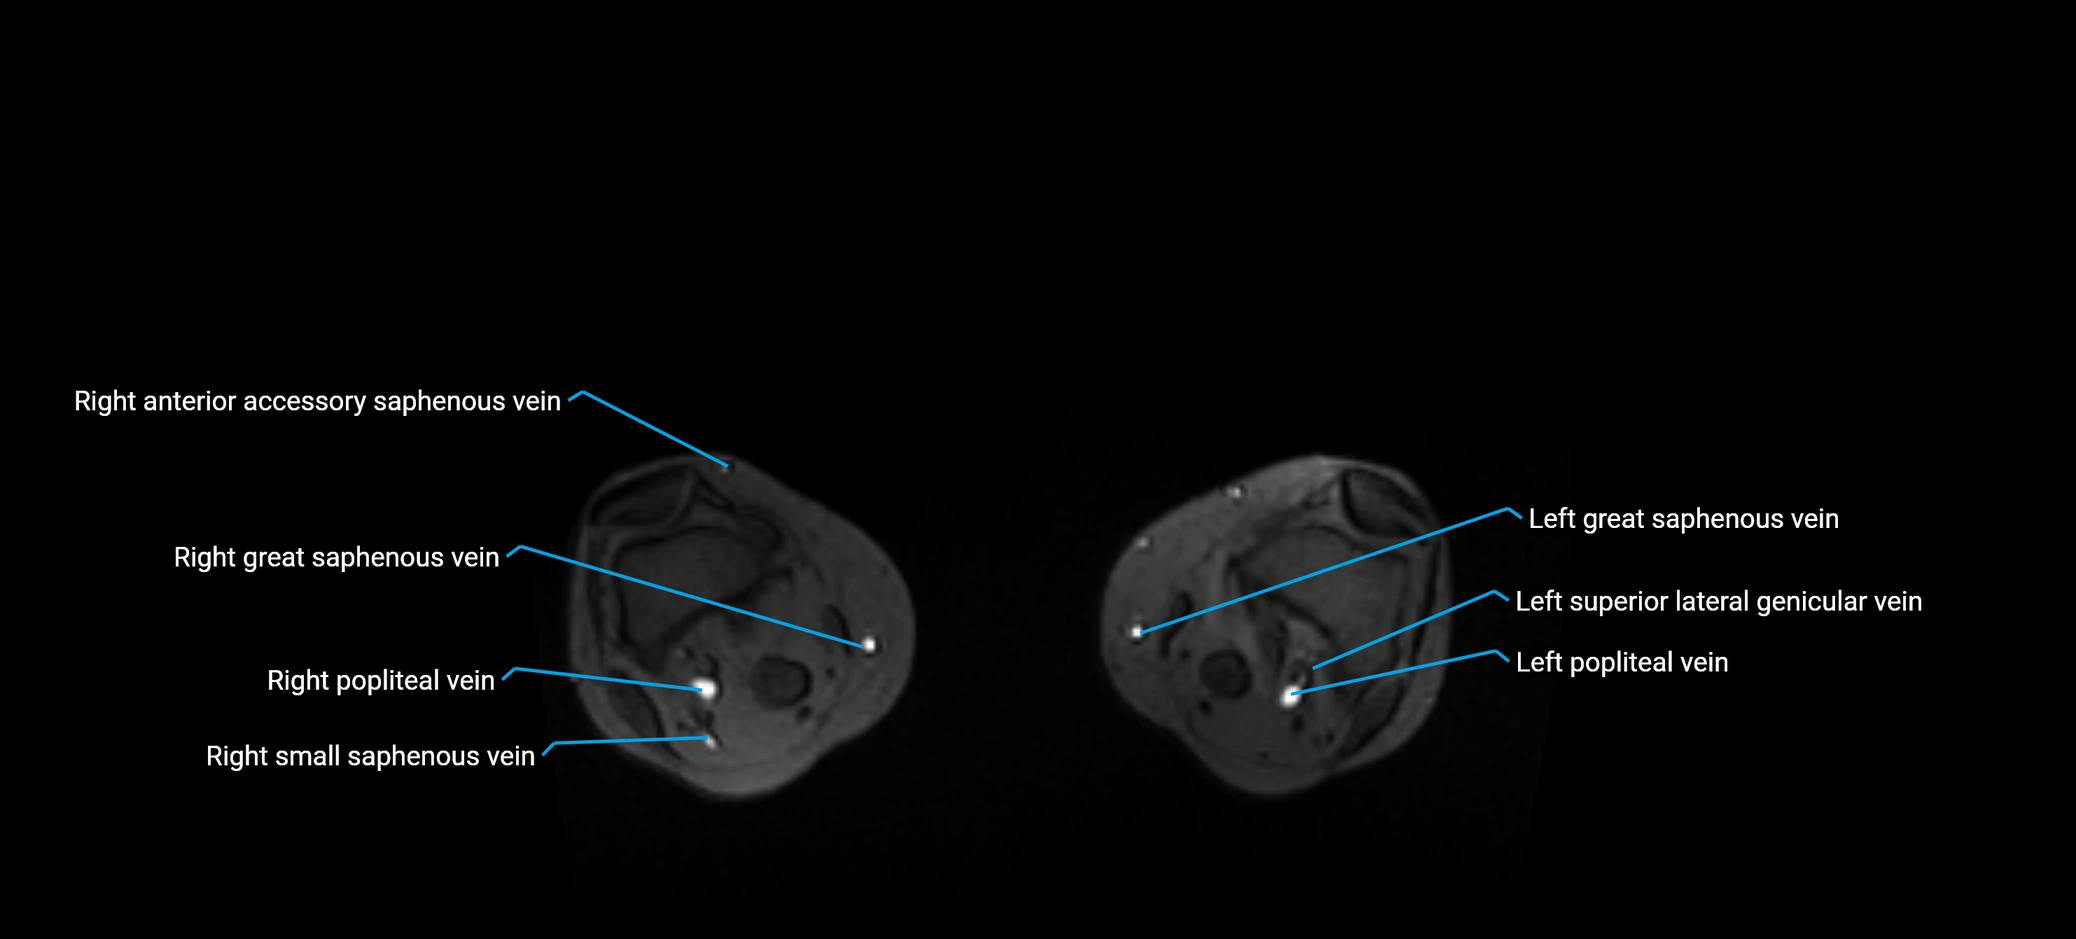

MRI image

image